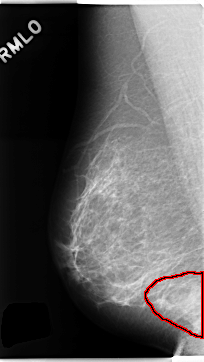

C_0251_1.RIGHT_MLO

RIGHT_MLO LINES 4704 PIXELS_PER_LINE 2640 BITS_PER_PIXEL 12 RESOLUTION 50 OVERLAY

FILE: C_0251_1.RIGHT_MLO.OVERLAY

TOTAL_ABNORMALITIES 1

ABNORMALITY 1

LESION_TYPE MASS SHAPE IRREGULAR MARGINS ILL_DEFINED

ASSESSMENT 4

SUBTLETY 5

PATHOLOGY BENIGN

TOTAL_OUTLINES 1

BOUNDARY